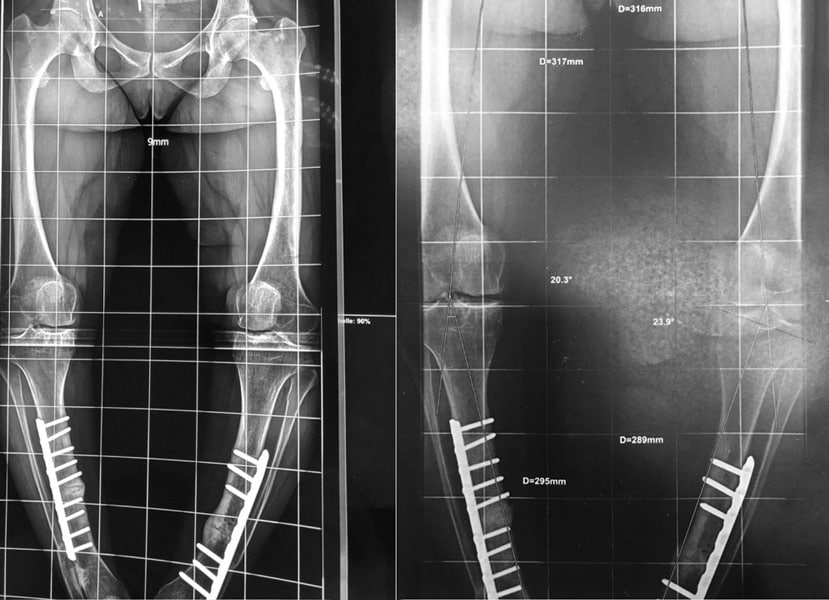

Déformation du genou en valgus (jambes en X), femme jeune (45 ans), ancienne handballeuse aux jeux de Séoul ; le fémur et le tibia sont déformés. Handicap majeur.

On réalise une double ostéotomie de varisation lors de la même opération, fémorale et tibiale, fixées avec des agrafes métalliques.